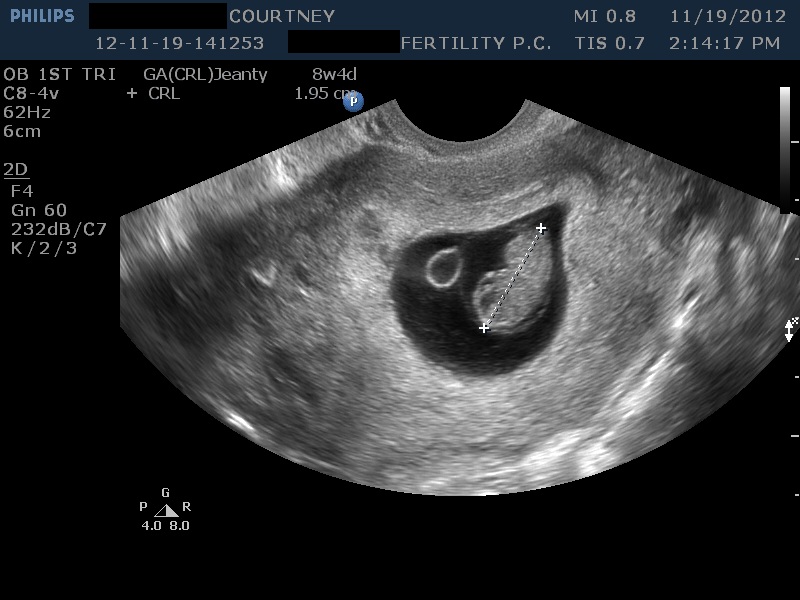

Анэмбриония узи

Анэмбриония узи 112 фотографий